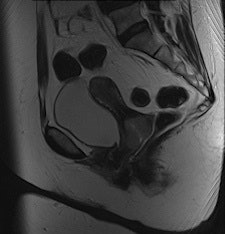

They found BLADE significantly (p < 0.0001) reduced motion and ghosting artifacts and showed improved conspicuity, but overall image quality did not differ significantly in the 47 patients who underwent sagittal BLADE and conventional TSE at 1.5-tesla after glucagon administration. In the majority of cases (53.2% versus 59.6%), radiologists preferred conventional TSE due to better image contrast and visibility of free pelvic fluid. Signal-to-noise ratio (SNR) and contrast-to-noise ratio (CNR) were significantly higher on conventional TSE.

"In our comparative study, the overall image contrast was reduced when using BLADE. This might be explained with the nonuniform T2-weighting along the width of the blade, i.e., the phase-encoding direction with contrast predominantly determined by low-frequency data as described by Pandit et al," Froehlich and colleagues wrote. "The reduced SNR and CNR in BLADE images occurred despite more frequent sampling of the k-space center. This was likely because the bandwidth in BLADE was twice as large as in conventional TSE (260 Hz per pixel in BLADE compared with 130 Hz per pixel in conventional TSE)."

There was also a lower angle used in BLADE (145°) compared with conventional TSE (170°) for the radiofrequency refocusing pulses in the TSE echo train, which may have resulted in reduced signal and T2-weighting in the BLADE images.

"Indeed, conventional T2-weighted TSE provided a significantly better visibility of free pelvic fluid or cystic structures (i.e., a relatively higher effective T2 weighting) in numerous cases," the researchers noted.